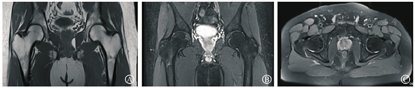

治疗上予非甾体消炎药物(塞来昔布)+降钙素类药物(依降钙素注射液,每周2次,肌肉注射)+骨化三醇胶囊,中医予草木犀流浸液片+中药(黄芪20 g、太子参15 g、玄参9 g、熟地15 g、茯苓10 g、生白芍10 g、桂枝9 g、山药9 g、川芎9 g、当归9 g、乳香9 g、鸡血藤15 g、川牛膝9 g、泽泻9 g、炙甘草9 g,以活血化瘀、补益肝肾、健脾祛湿)的联合治疗。治疗2个月后,患者于2019年3月复诊时诉症状消失。嘱患者继续服药巩固治疗,于2019年6月复查双侧髋关节MRI见右侧髋关节少量积液。右侧股骨头痊愈(图5)。复查骨密度未见骨质疏松。